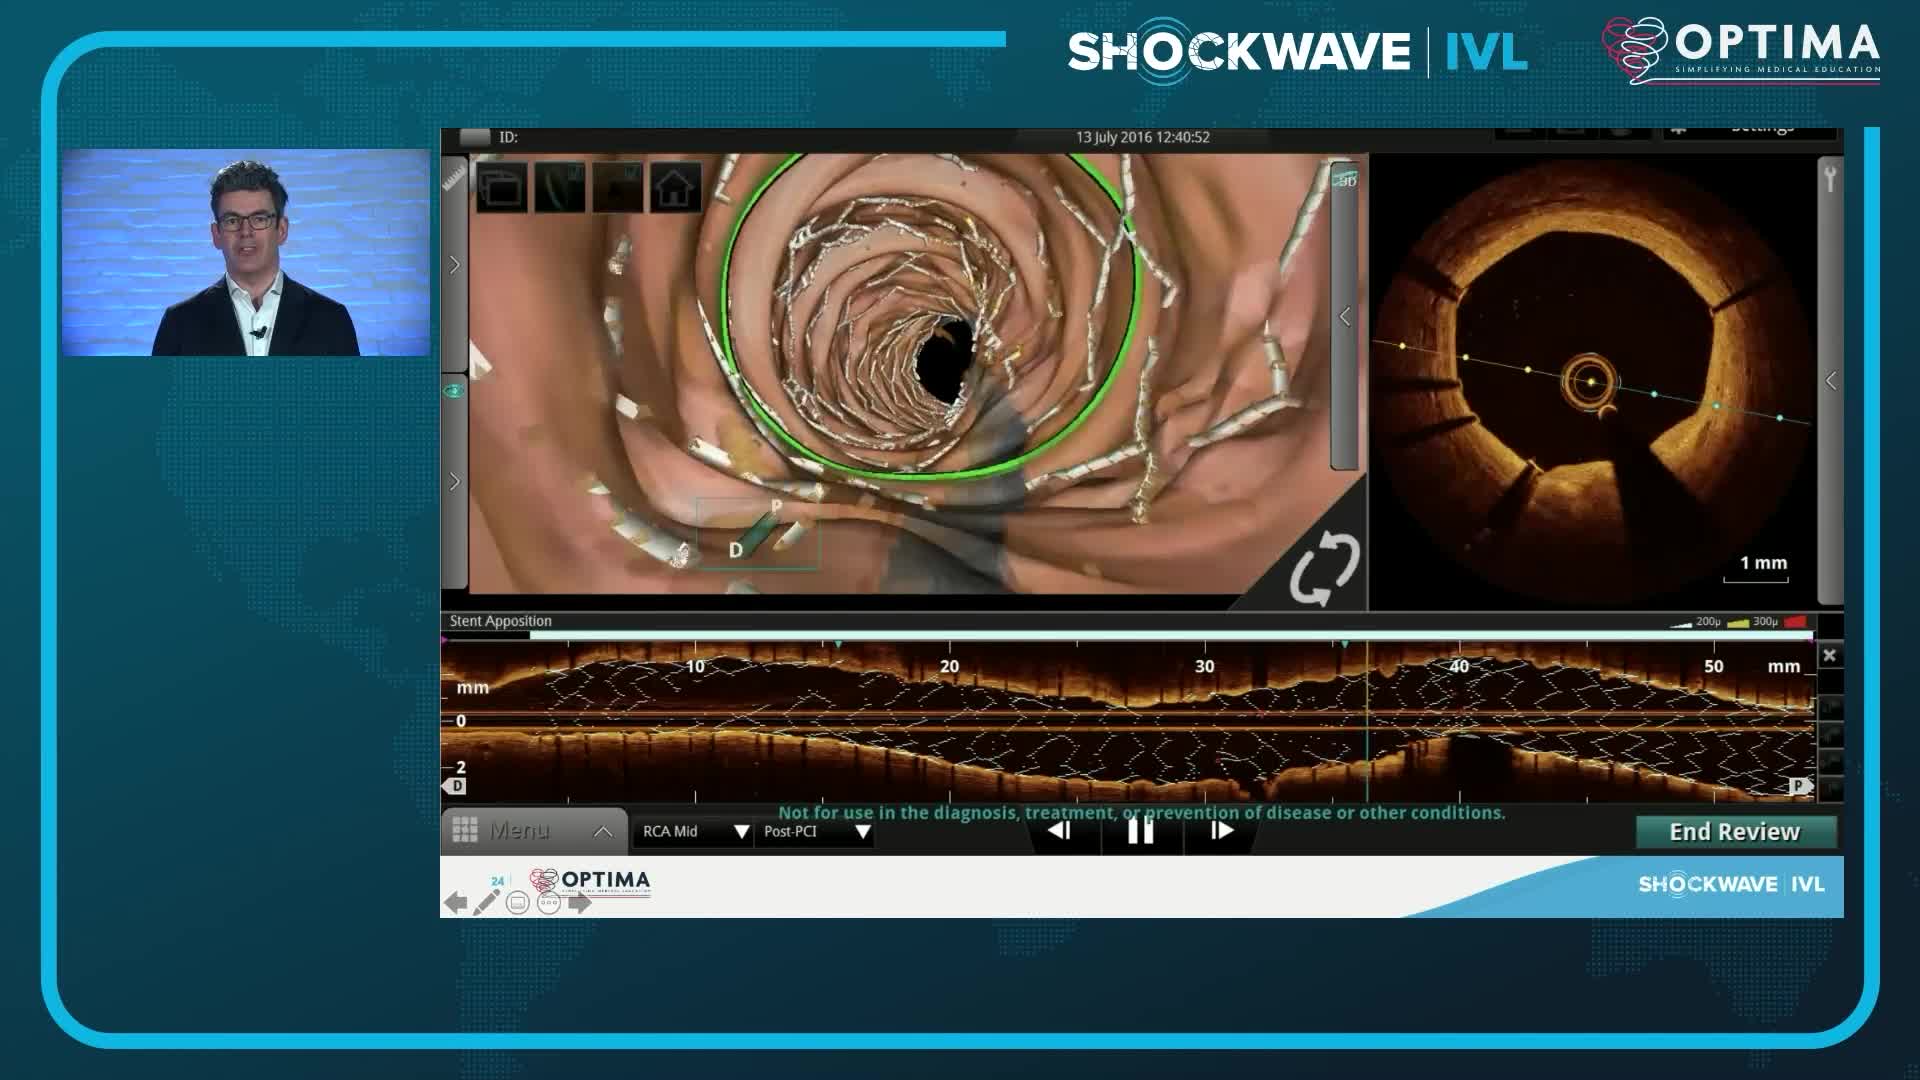

Calcium Masterclass with Shockwave IVL

Treatment of coronary arterial calcium (CAC) has being redefined. We explore the interaction between CAC and patient...

The integrated use of physiology and imaging is transforming the treatment of complex bifurcation disease. We explore...